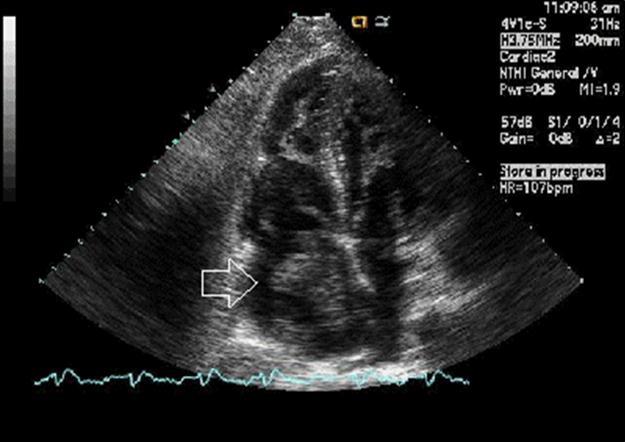

Echocardiogram shows: 1. Severely decreased LV ejection fraction. 2. Large, mobile thrombus in the right atrial cavity (Figure 1). 3. Moderately dilated right atrium. 4. Mild aortic regurgitation. 5. Mild concentric left ventricular hypertrophy. 6. The left ventricular size is mild to moderately increased. 7. Mild thickening of the anterior and posterior mitral valve leaflets. 8. Ischemic cardiomyopathy. 9. Mild aortic valve sclerosis without stenosis. 10. Mild mitral valve regurgitation. 11. Mildly elevated pulmonary artery systolic pressure. 12. Moderately enlarged right ventricle. 13. Moderately reduced RV systolic function.

Figure 1.Echographic image of Case 1 of the large, mobile thrombus in the right atrial cavity.